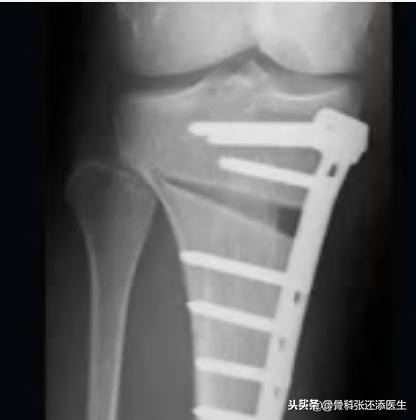

膝关节周围截骨术(HTO):这个手术主要矫正力线的不正常。就像桌子,一边高一边低,将低的那边踮高固定,桌子就重回稳定状态了。膝关节也一样,膝关节不平衡,导致力线不正常(髋关节到膝关节再到踝关节应该能以一条直线贯通,称为力线),从而加重磨损退变和疼痛产生。

总结:这个部分,主要适合中晚期的病友,关节已经比较疼痛,在保留膝关节的同时,借助手术进行处理,以解决疼痛问题

截骨手术